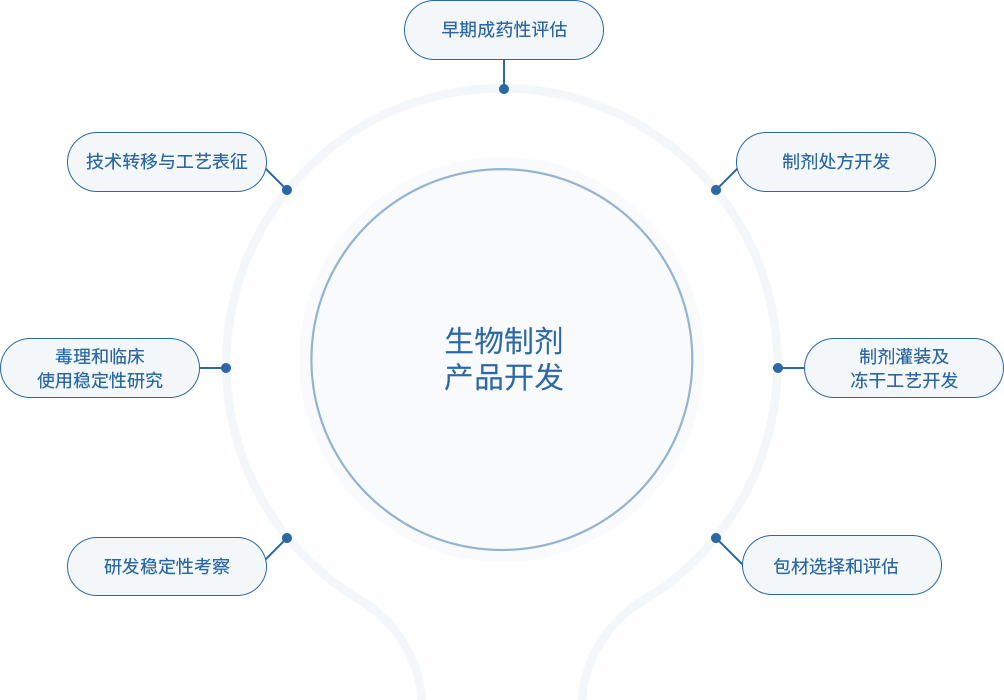

е…Ёж–№дҪҚе®ҡеҲ¶еҢ–з”ҹзү©еҲ¶еүӮдә§е“ҒејҖеҸ‘жңҚеҠЎ

В· з¬јзҪ©з§Қз§ҚйҖҡдҫӢе’ҢжҢ‘жҲҳжҖ§еҲ¶еүӮзӯүејҖеҸ‘ пјҢпјҢ пјҢ пјҢпјҢеҰӮж¶ІдҪ“еҲ¶еүӮеҶ»е№ІеҲ¶еүӮгҖҒеӨҡеүӮйҮҸйј»е–·е’Ңй«ҳжө“еәҰж¶ІдҪ“еҲ¶еүӮзӯү

В· е…јйЎҫз§Қз§Қз»ҷиҚҜйҖ”еҫ„ пјҢпјҢ пјҢ пјҢпјҢеҰӮйқҷи„үжіЁе°„гҖҒзҡ®дёӢ/иӮҢиӮүжіЁе°„гҖҒйј»и…”зӯү

В· з¬јзҪ©з§Қз§ҚеҲҶеӯҗзұ»еһӢзҡ„еҲ¶еүӮејҖеҸ‘ пјҢпјҢ пјҢ пјҢпјҢ еҰӮеҚ•жҠ—гҖҒеҸҢжҠ—гҖҒиһҚеҗҲеҚөзҷҪгҖҒ еҒ¶иҒ”иҚҜзү© (ADCгҖҒRDCгҖҒAOCзӯү)гҖҒзәізұіи„ӮиҙЁдҪ“(mRNA-LNP)зӯү